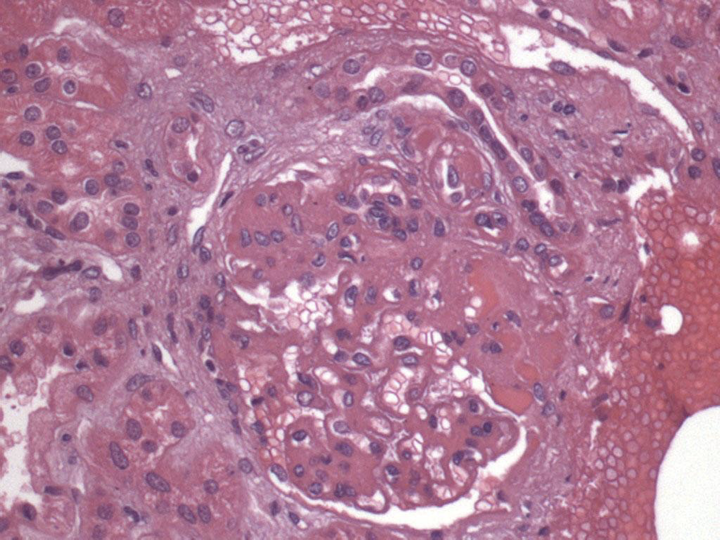

문제 5. 이 이미지의 조직병리학적 진단은 무엇입니까?

답 5. 국소 분절성 사구체 경화증